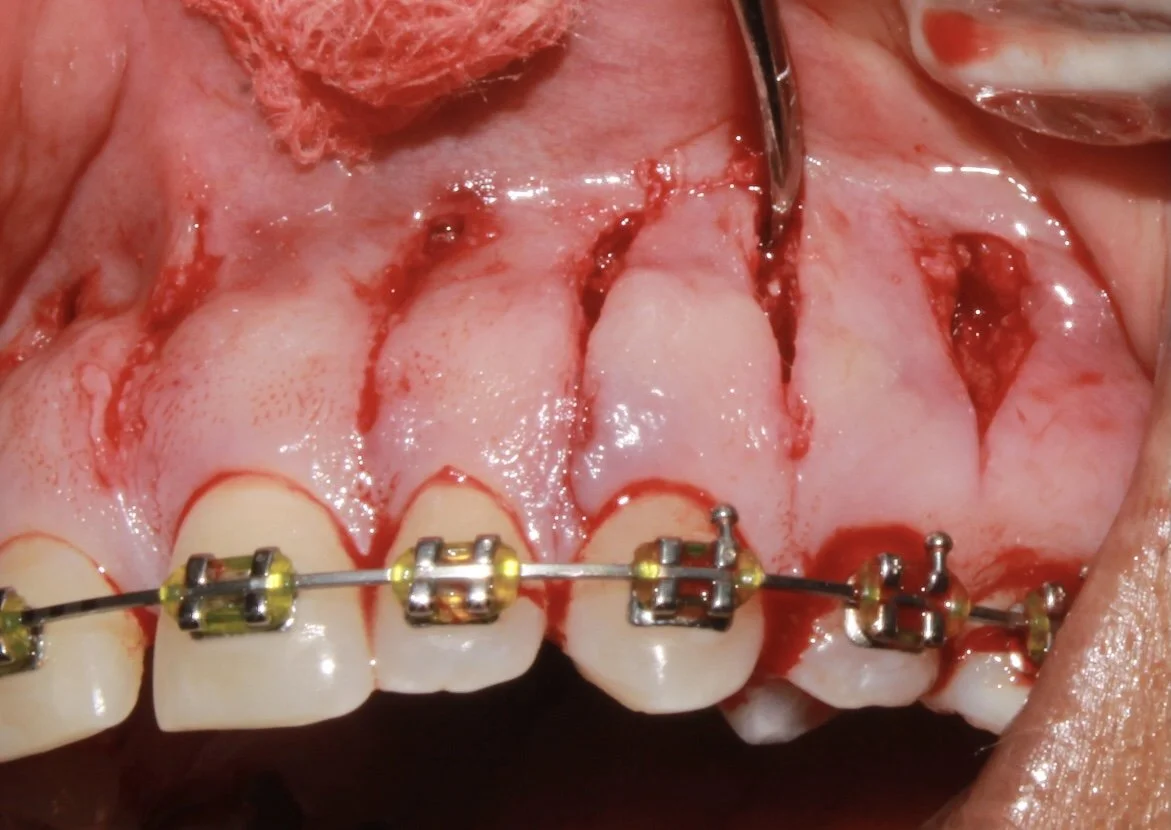

ACCELERATING ORTHODONTICS - FASTENING THE TOOTH MOVEMENTS

ACCELERATING ORTHODONTICS - FASTENING THE TOOTH MOVEMENTS